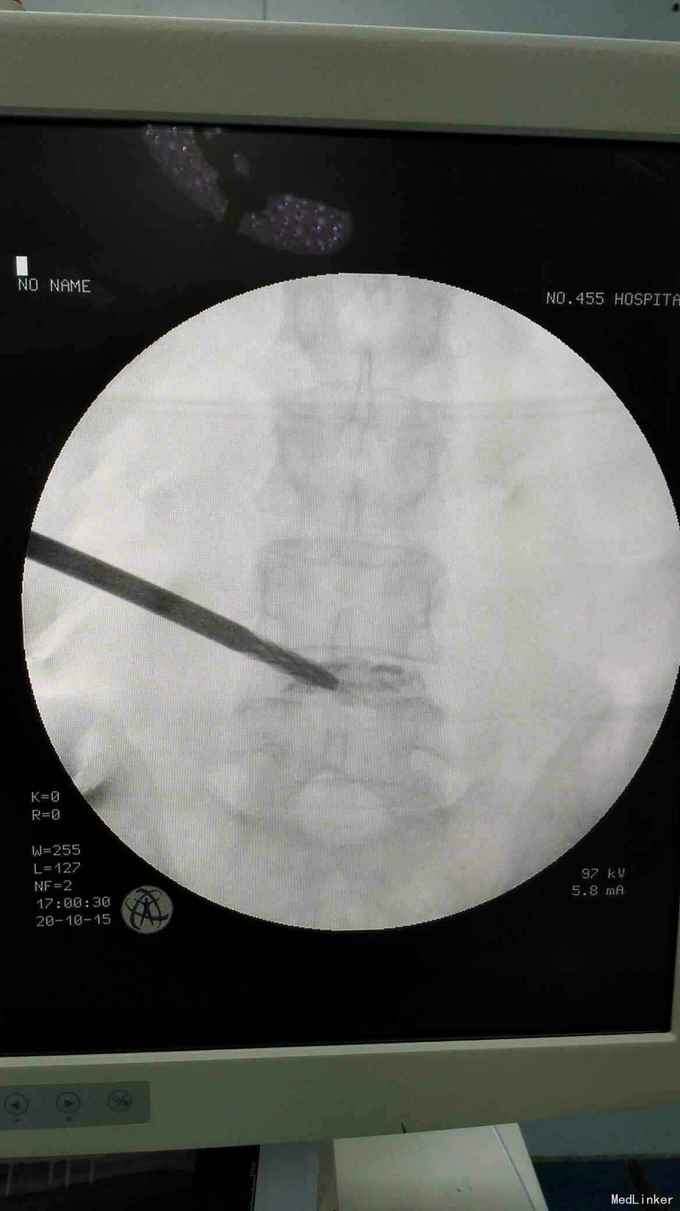

考虑腰椎间盘突出伴椎管狭窄症。行椎间孔镜下髓核摘除,椎间孔成形。

术后患者症状消失。 目前脊柱内镜的应用越来越广泛,随着手术技术的进步可以很好解决部分椎管狭窄的问题。